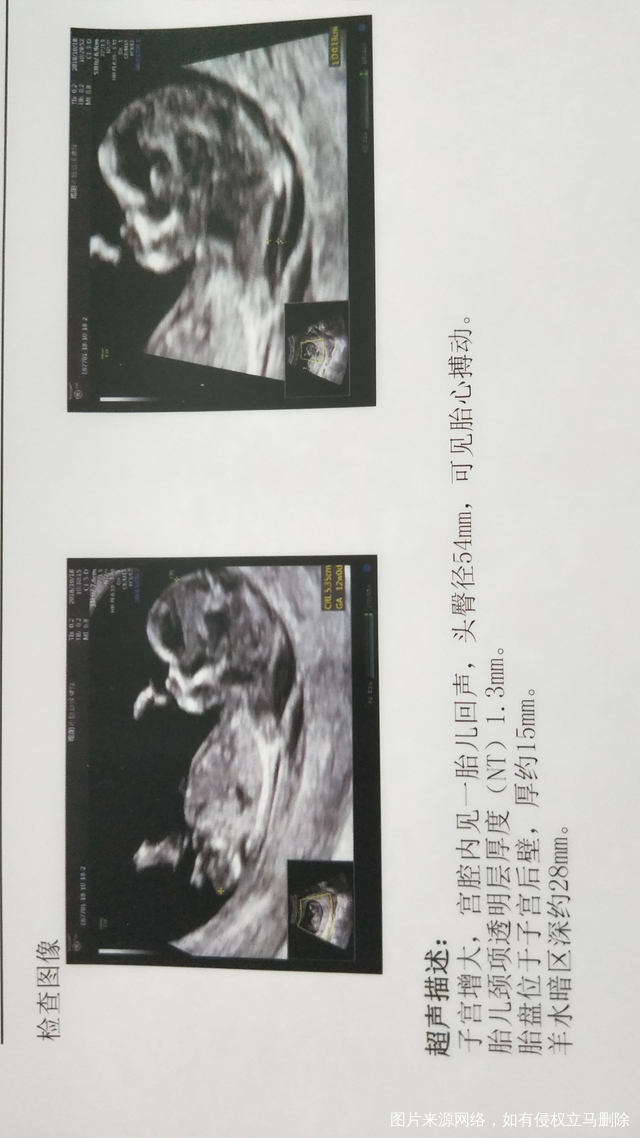

12周做nt的时候,刚进入诊室,医生说第几胎,我说3胎。医生:怎么都生那么多,我笑:没办法,查了有一下,医生:前2胎是不是都是妹妹呢?我:是的!医生嗯,没说话了!亲们,你们说医生会不会是在暗示宝宝的性别呢?但是才12周,看得出来吗?(附上12周nt的单)